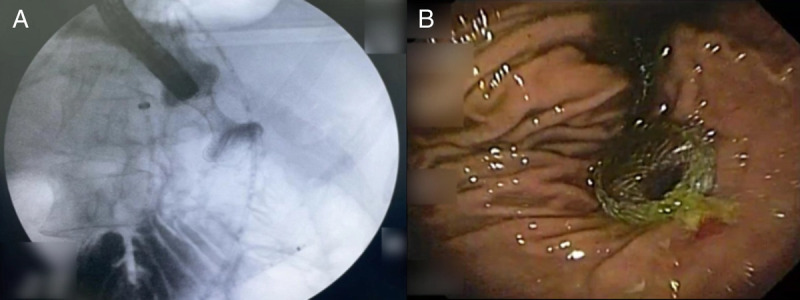

Double EUS-guided bypass for gastric outlet and biliary tract malignant obstruction: A standardized one-step approach (with videos).